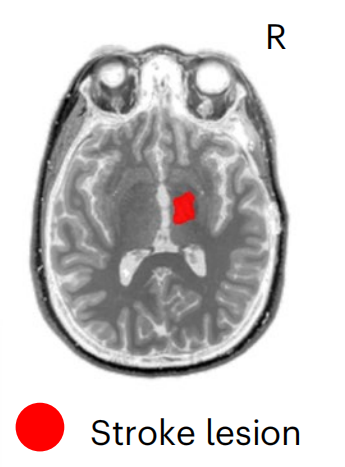

病例1:女,31岁,在参与该研究的九年前,因海绵状畸形继发于右侧丘脑出血性中风,病变局限于内囊、中脑和脑桥,FAS=0.17,Fugl-Meyer运动评估显示中度损伤。 病例2:女,47岁,在参与本研究的三年前,因右颈动脉夹层导致右侧缺血性大脑中动脉(MCA)卒中,导致大面积MCA梗死。SCS01的,病变范围较大,影响右半球的放射冠,FAS=0.35,Fugl-Meyer运动评估显示重度损伤。 SCS01 SCS02 治疗方案